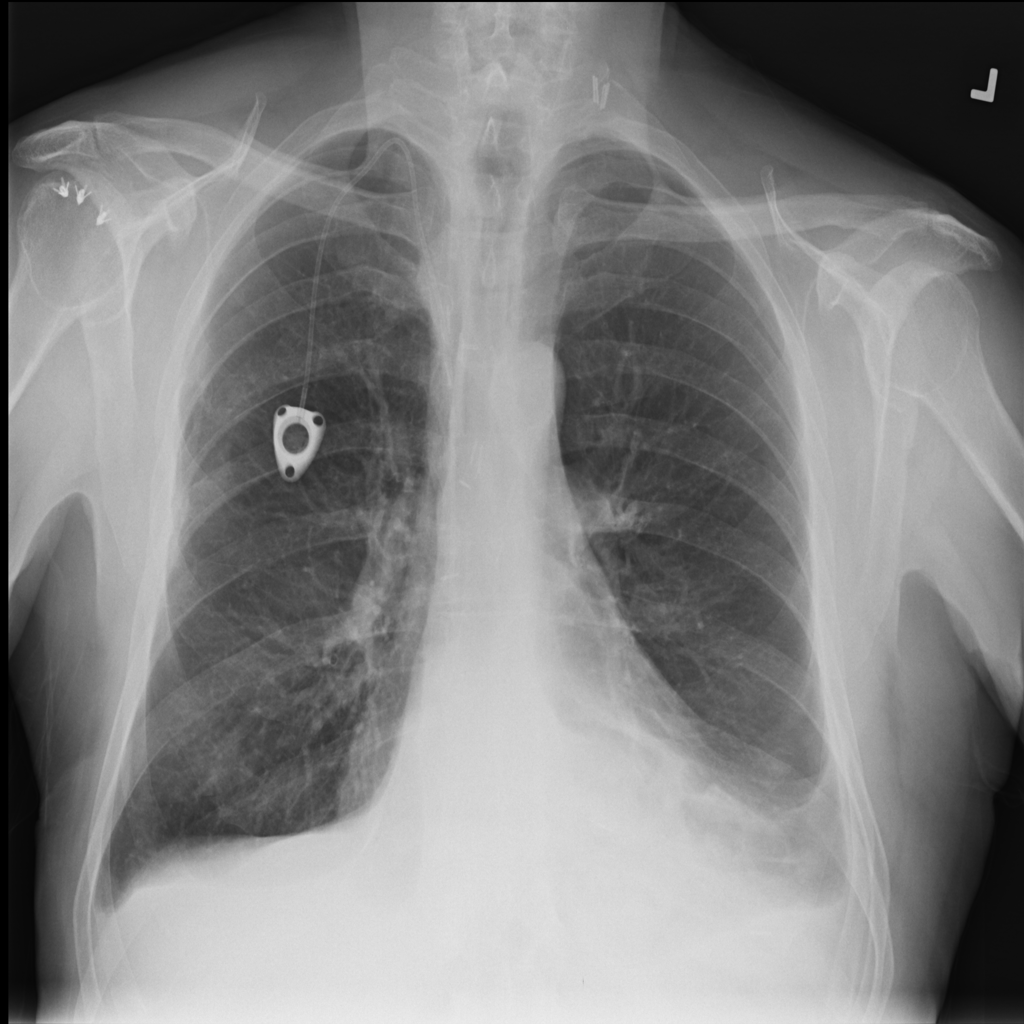

PAT-0ABD · IMG-000Hernia

PAT-0ABD · IMG-000

PA